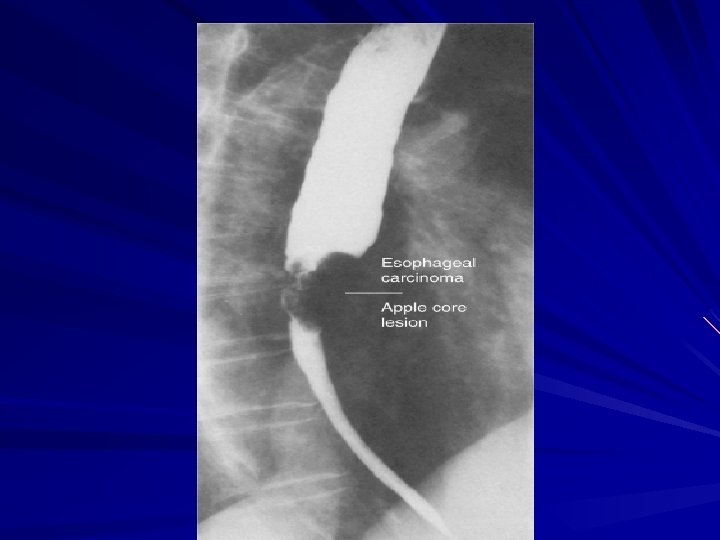

Esophagram A barium esophagram is recommended for any patient presenting with dysphagia is able to differentiate intraluminal from intramural lesions and to discriminate between intrinsic (from a mass protruding into the lumen) and extrinsic (from compression of a structures outside the esophagus) compression

Esophagram The classic finding of an apple-core lesion in patients with esophageal cancer is recognized easily Although the esophagram will not be specific for cancer, it is a good first test to perform in patients presenting with dysphagia and a suspicion of esophageal cancer